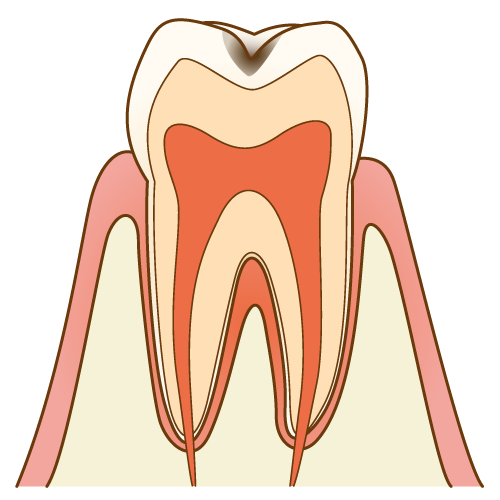

むし歯(虫歯)

進行すると、歯にできた穴に食べかすや細菌が溜まり、腐敗することで口臭を発生させます。 歯科医院でのむし歯治療をする必要があります。